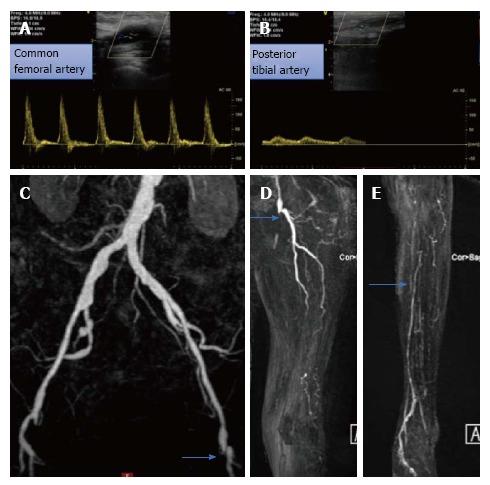

Patients with critical limb ischemia necessitate immediate intervention to restore blood flow to the affected limb. Endovascular procedures are currently preferred for these patients. We describe the case of an 80-year-old female patient who presented to our department with ischemic rest pain and ulceration of the left limb. The patient had history of left femoral popliteal bypass surgery, femoral thromboendarterectomy and patch angioplasty of the same limb 2 years ago. Doppler sonography and magnetic resonance angiography revealed an occlusion of the left superficial femoral artery (SFA) and popliteal artery and of all three infra-popliteal arteries. Due to severe comorbidities, the patient was scheduled for a digital subtraction angiography. An antegrade approach was first attempted, however the occlusion could not be passed. After revision of the angiography acquisition, a stent was identified at the level of the mid SFA, which was subsequently directly punctured, facilitating the retrograde crossing of the occlusion. Thereafter, balloon angioplasty was performed in the SFA, popliteal artery and posterior tibial artery. The result was considered suboptimal, but due to the large amount of contrast agent used, a second angiography was planned in 4 wk. In the second session, drug coated balloons were used to optimize treatment of the SFA, combined with recanalization of the left fibular artery, to optimize outflow. The post-procedural course was uneventful. Ischemic pain resolved completely after the procedure and at 8 wk of follow-up and the foot ulceration completely healed.

严重肢体缺血患者需要立即进行干预以恢复患肢的血流。目前,血管内介入手术是这类患者的首选治疗方法。我们描述了一名80岁女性患者的病例,该患者因左下肢缺血性静息痛和溃疡前来我院就诊。患者2年前曾接受左股腘动脉搭桥手术、股动脉血栓内膜切除术及同肢体的补片血管成形术。多普勒超声和磁共振血管造影显示左股浅动脉(SFA)、腘动脉以及所有三支腘下动脉均闭塞。由于存在严重的合并症,该患者计划接受数字减影血管造影检查。首先尝试顺行入路,但闭塞部位无法通过。在重新评估血管造影图像后,发现在SFA中段水平有一枚支架,随后直接对其进行穿刺,从而实现了闭塞部位的逆行通过。此后,对SFA、腘动脉和胫后动脉进行了球囊血管成形术。结果被认为不太理想,但由于使用了大量造影剂,计划在4周后进行第二次血管造影。在第二次手术中,使用药物涂层球囊对SFA进行优化治疗,并对左腓动脉进行再通以优化流出道。术后过程顺利。术后缺血性疼痛完全缓解,随访8周时足部溃疡完全愈合。